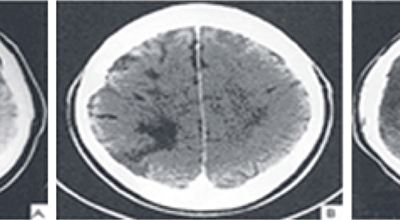

뇌조직은 평소에도 다량의 혈류를 공급받고 있는데 어떤 여러가지 원인으로 인해서 뇌혈관에 이루는 관이 막히는 경우 뇌에 공급되는 혈액량이 떨어지면서 뇌조직이 기능을 제대로 하지 못하게 되는데 이렇게 뇌혈류 감소가 일정 시간 이상 지속되다 보면 뇌조직의 괴사가 시작되어 회복 불가능한 상태가 되는데 이를 뇌경색이라 해요. 오늘 알아볼 질병은 뇌경색 초기증상이예요.

뇌경색의 경색이란 허혈성 괴사를 말해요. 여기서 허혈이란 혈관이 막히는 것을 말하고 괴사는 말 그대로 일부가 죽는 것을 말하는데 뇌경색의 경우 뇌의 혈관이 막혀 뇌세포 일부가 죽는 걸 의미해요. 뇌혈관이 막혔다 해서 혈액 공급이 안되는것은 또 아니에요.

막힌 혈관으로도 혈액이 공급되긴 하나 혈관이 막혀있어 혈액을 보내긴 하나 제대로 흐르지 못하고 혈액이 쌓이고 축적되어 물풍선에 물이 꽉 차서 터지듯 뇌혈관이 터지는 경우가 일어날 수 있는데 이를 뇌출혈 이라고 해요. 물론 외상으로 인한 뇌출혈도 있지만 이처럼 뇌경색으로 인해 혈관이 막혀 터지는 경우도 있어요.